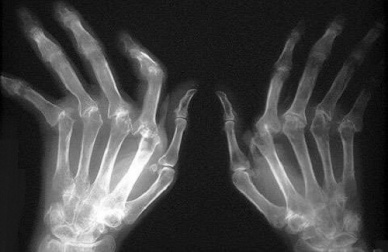

In alcuni casi, possono anche comparire noduli reumatoidi, protuberanze sulla pelle (specialmente sul dorso di mani e piedi) o all’interno del corpo. Quando la malattia si trova in uno stadio avanzato, l’infiammazione dà luogo alla deformazione delle articolazioni.